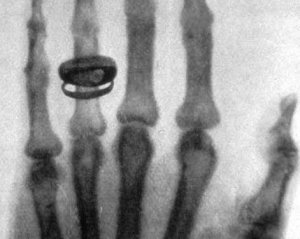

Через 50 дней ученый представил председателю Вюрцбургского физико-медицинского общества рукопись из 17 страниц, содержит описание открытых им лучей. Вместе с рукописью ученый представил также первую рентгенограмму, сделанное ранее, 22 декабря, на которой была запечатлена рука его жены Берты Рентген.